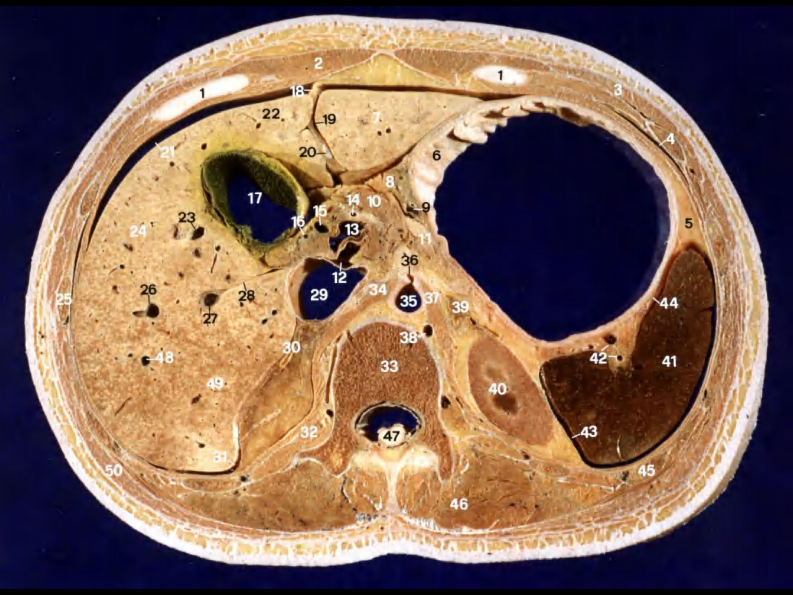

10 胰和肝外胆道断层解剖及CT.pdf